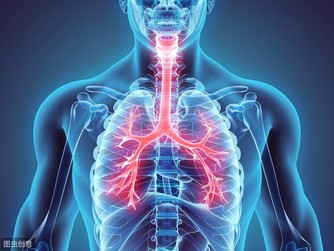

氣促:肺癌的早期跡象

呼吸急促可能是肺癌的表現。

如果咳嗽了好幾周都沒好,不管是乾咳還是咳中帶痰,

都有可能是肺癌的早期跡象,

建議及時就醫,拍X光片、做CT等檢查。